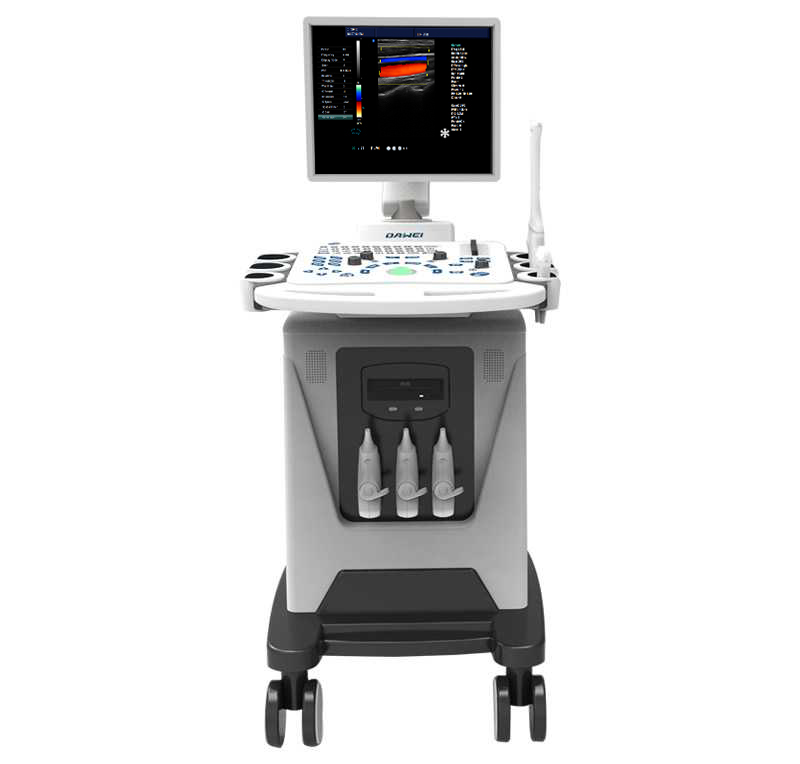

人性化設計的操作面板

符合人類工程學

一鍵調節/ 操作方便/布局簡潔/ 設計新穎

探頭---寬頻多頻率

硅膠按鍵---方便快捷調控

手腕支撐---減輕壓力損傷

探頭盒---掛鉤式人性化設計